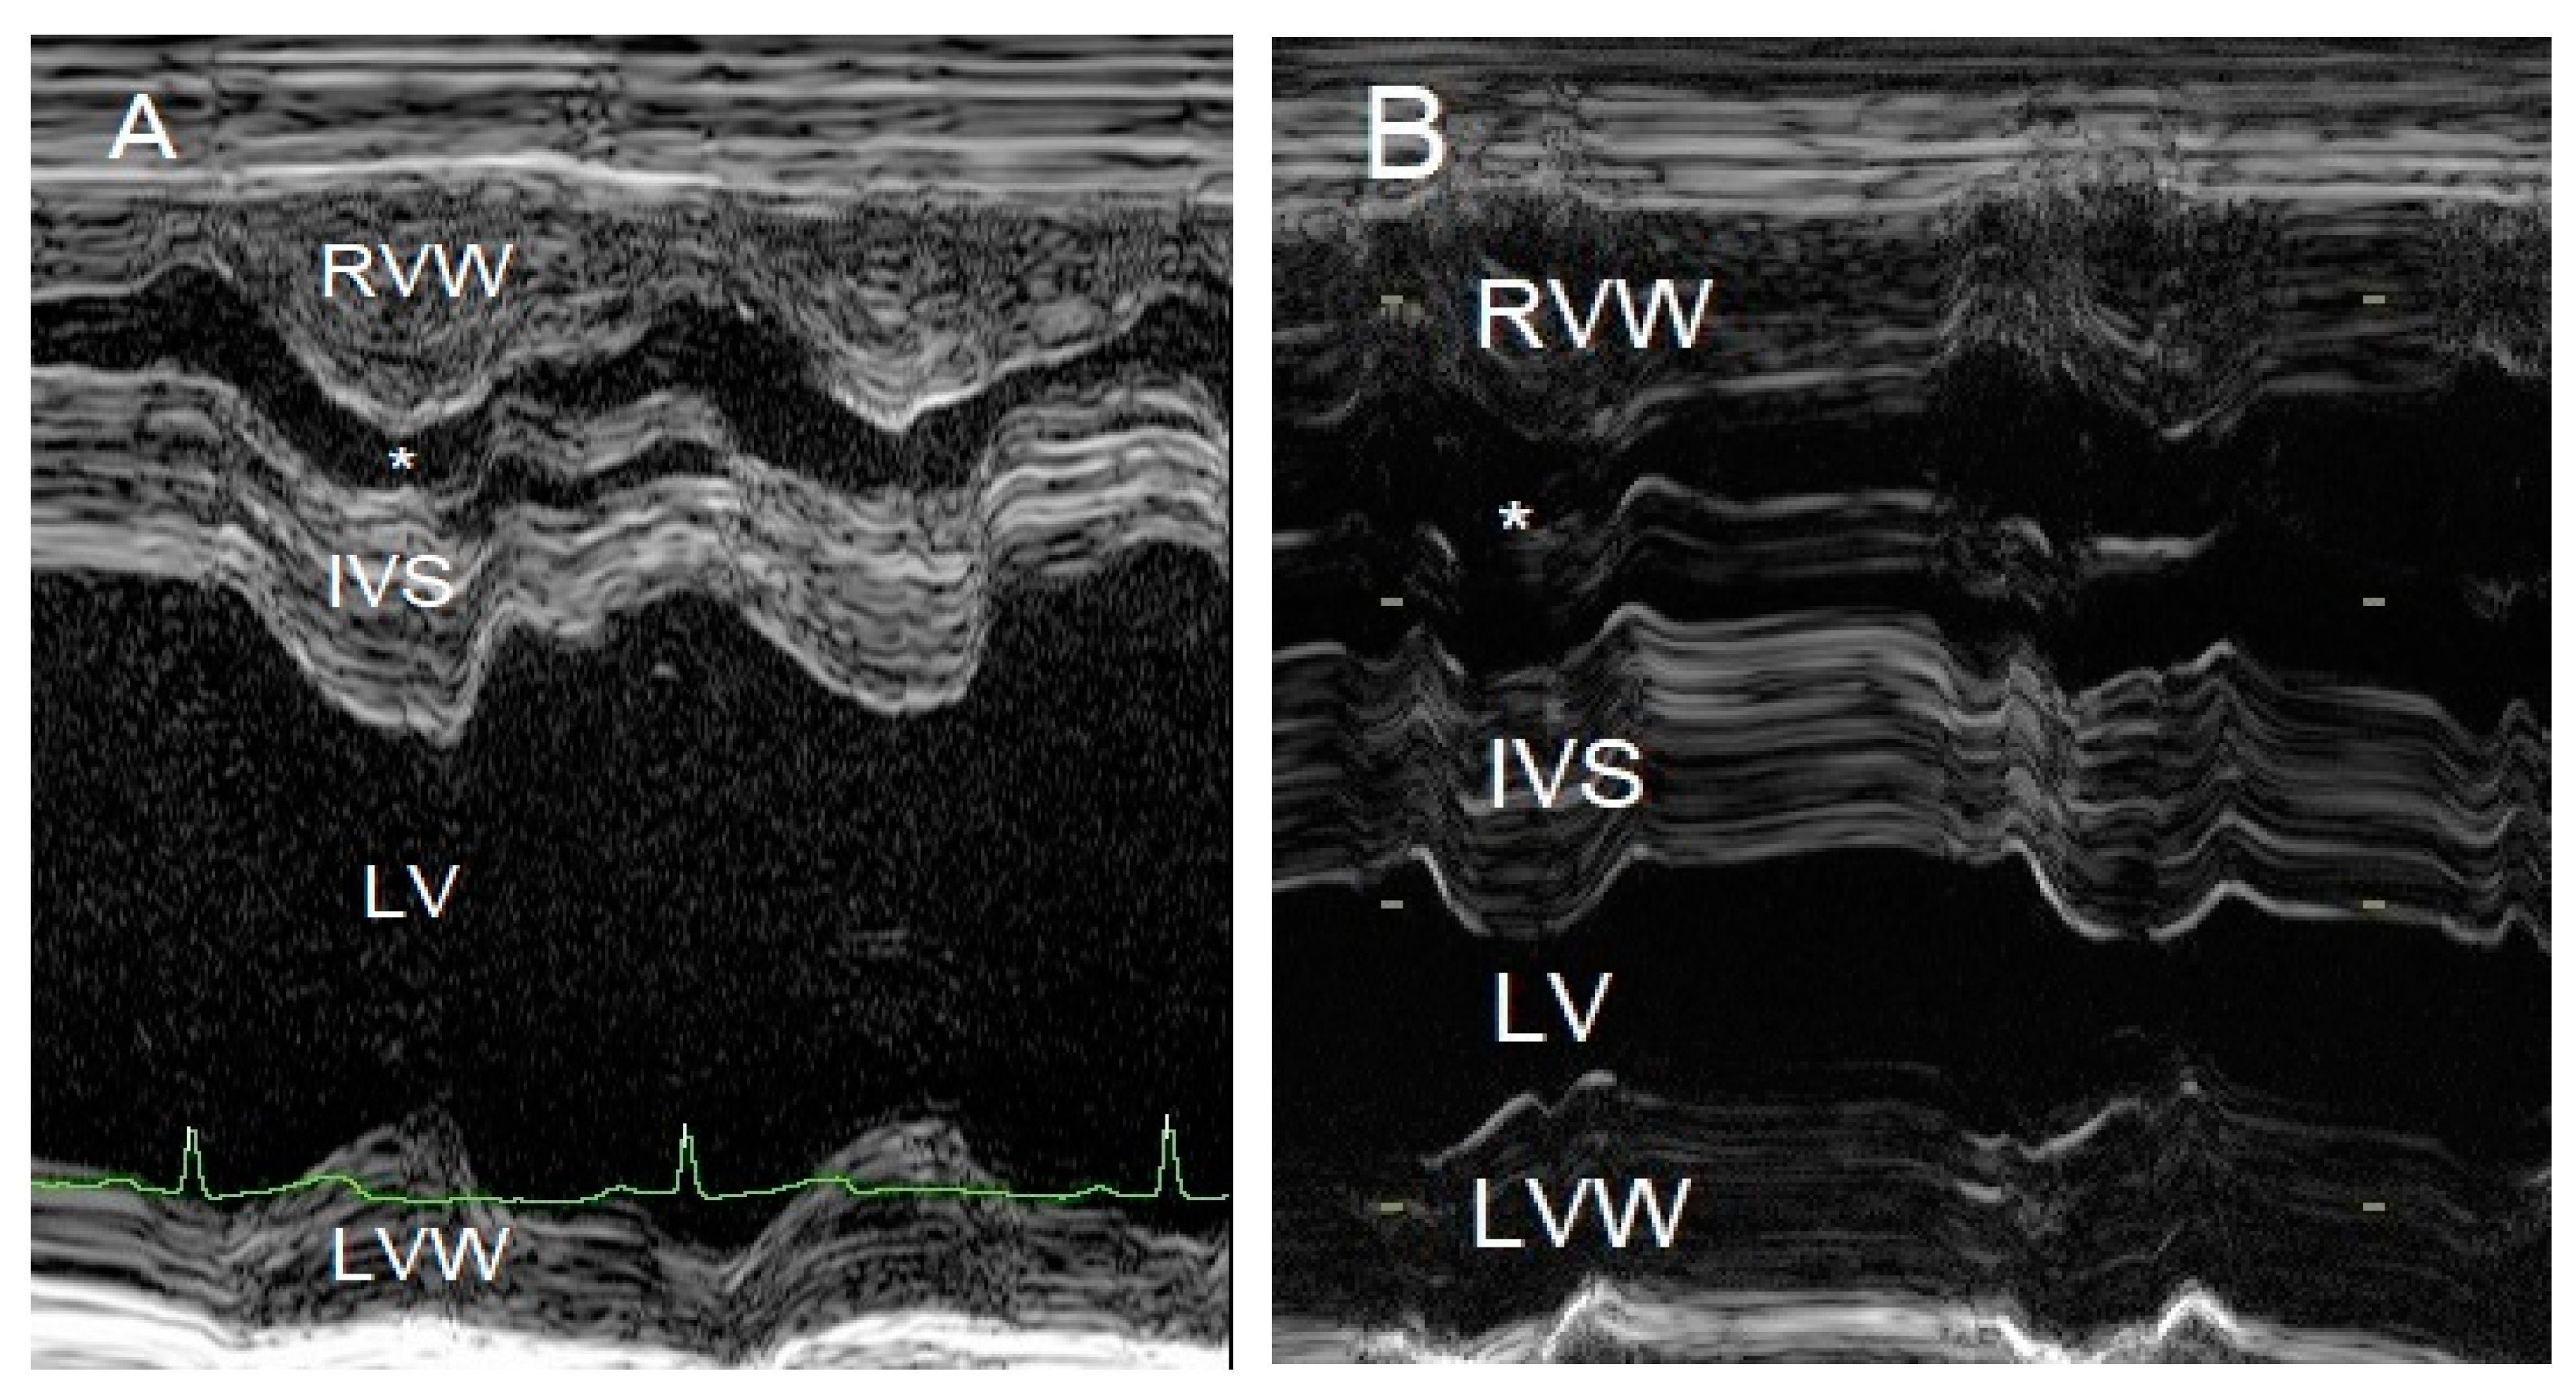

To evaluate the cause of the murmur and the cause of the dyspnea after having obtained thoracic radiographs, an echocardiography was performed in an awake dog without sedation. Echocardiography showed a severe localized right ventricular concentric hypertrophy and a severe obstruction of the right ventricular outflow tract caused by a localized muscular hypertrophy within the right ventricle (Figure 3). The right ventricular lumen at the level of the obstruction measured 1.2 mm, and continuous wave Doppler interrogation revealed a pressure gradient of at least 88 mmHg between the proximal high-pressure and the distal normal-pressure right ventricular compartments. The pulmonary artery and pulmonary valve looked normal, with an annulus diameter of 8 mm and with a normal peak flow velocity of 1.1 m/s (Figure 3). There was no tricuspid valve regurgitation present. The right atrium was subjectively mildly dilated. The left ventricle and left atrium were underfilled (Figure 4). There was a trivial aortic valve regurgitation present, probably secondary to the VSD, since the aortic valve leaflets looked normal. The aortic root diameter was 10 mm. Just underneath the aortic valve, a VSD was seen with a diameter of about 2.5 mm, and color Doppler revealed right-to-left shunting from the high-pressure compartment of the right ventricle to the left ventricle with a pressure gradient of 13 mmHg. A bubble study, i.e., injection of agitated physiologic saline solution intravenously, confirmed the right-to-left shunting at the level of the ventricles (Figure 5). There were no ascites or hepatic venous congestion present.

Figure 4. M-mode echocardiographic images of the right and left ventricles at 10 weeks of age (A) and 3 years of age (B). The most striking difference is the reduced left ventricular chamber (LV) size from normal to too small and the enlargement of the right ventricular chamber (*) caused by a mixed concentric and eccentric hypertrophy. The left ventricular diastolic chamber dimension at 10 weeks of age was 18.7 mm, and this value became 9.9 mm at 3 years of age. Annotations are placed on structures in systole: RVW—right ventricular free wall; IVS—interventricular septum; LVW—left ventricular free wall.